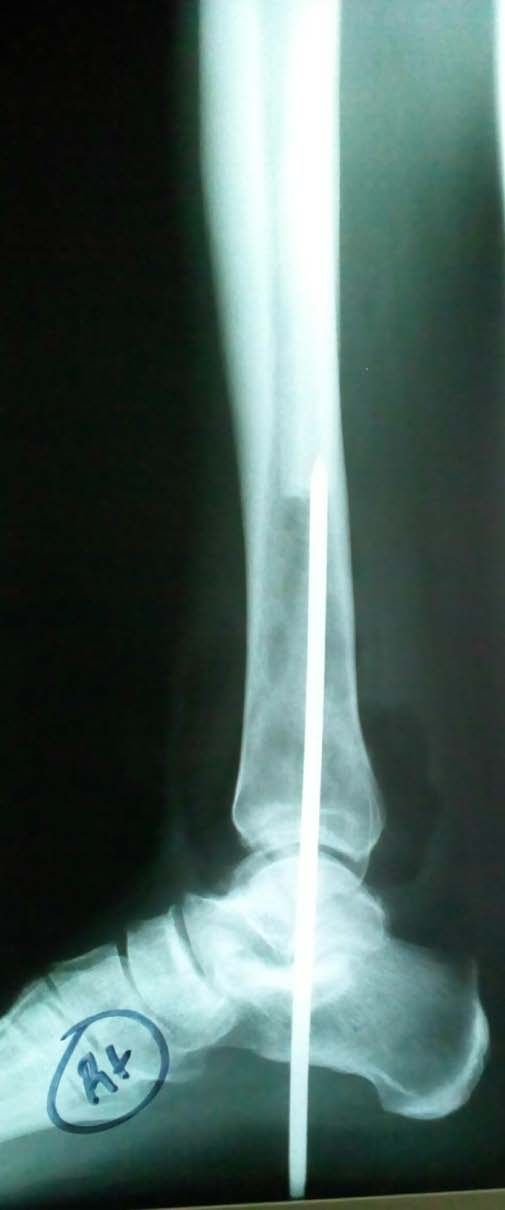

Core needle biopsy suggested a chondromyxoid fibroma. Preoperatively a staged procedure was planned because of the following factors: 1) The rarity of the diagnosis of chondromyxoid fibroma of the lateral malleolus, 2) The soft tissue invasion and 3) Chondromyxoid fibroma may be confused with malignancies histologically. The plan was for definitive histology to be obtained prior to performing a definitive procedure. Stage one consisted of an enblock excision and Steinmann pin stabilisation of the ankle. Stage two would have been definitive ankle arthrodesis using large fragment cancellous screws, if the post excision histology confirmed a benign tumour. Via a lateral approach (see fig. 3), the fibula was resected 3 cm proximal to the gross tumour (see fig. 4). The distal resection was just distal to the fibular tip. The lateral ligamentous complex was not readily discernible due to scar tissue. There was cortical irregularity of the tibia (see fig. 5) adjacent to the tumour. It was uncertain as to whether or not this was due to a simple mass effect of the distal fibular tumour. Grossly, a complete en-block resection was achieved (see fig. 6). The histological diagnosis remained unchanged post excision. Initial postoperative radiographs demonstrated a reduced ankle as well as complete tumour resection (see fig. 7 and fig. 8). The wound took twelve weeks to heal and the Steinmann pin was left in situ over that duration. At the two year follow up assessment; his ankle and subtalar joints remained stiff however he did not have any complaints in terms of functional limitation. C year. The pain was worse at night and after prolonged enlargement towards local tissues. According to the world health organization; it is a benign tumour with areas which are lobulated and has zones which are round or fusiform separated by abundant intercellular myxoid, chondroid and fibrinoid material as well as varying forms of multinucleated cells (1). The fibrotic areas are as a result of repair of degenerated areas and the myxomatous zones are as a result of necrosis of the chondroid tissue (1). The tumour is more common in males and it is most commonly located in the proximal tibia, distal femur, pelvis and foot (2). Histologically, it is not uncommon to be confused with more aggressive tumours. Chondromyxoid fibromas when treated by excision do not tend to recur and there are no reports of metastasis (2).